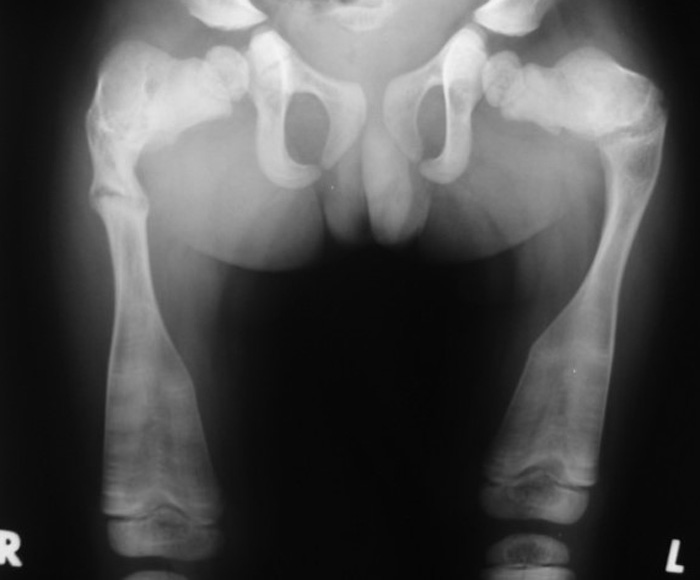

<p>What is the name of this pathology?</p>

What is the name of this pathology?

Osteogenic Imperfecta